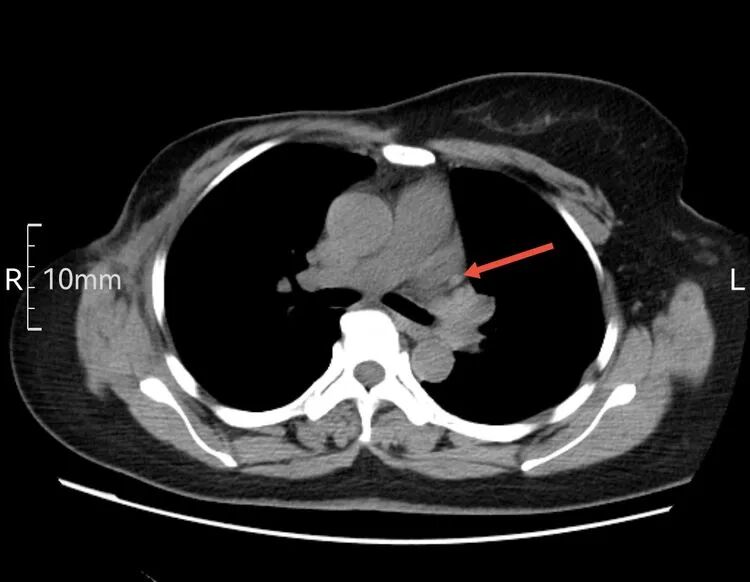

以下是患者的CT表现:

箭头所指为左侧“上腔静脉”走行  虽然过程不寻常,但在血管造影辅助下显示其“真容”后,导管经左侧颈内静脉,避开变异的“左上腔静脉”并通过左侧头臂干,导管头端留置在正常的上腔静脉内。成功给予患者植入左侧胸壁港。